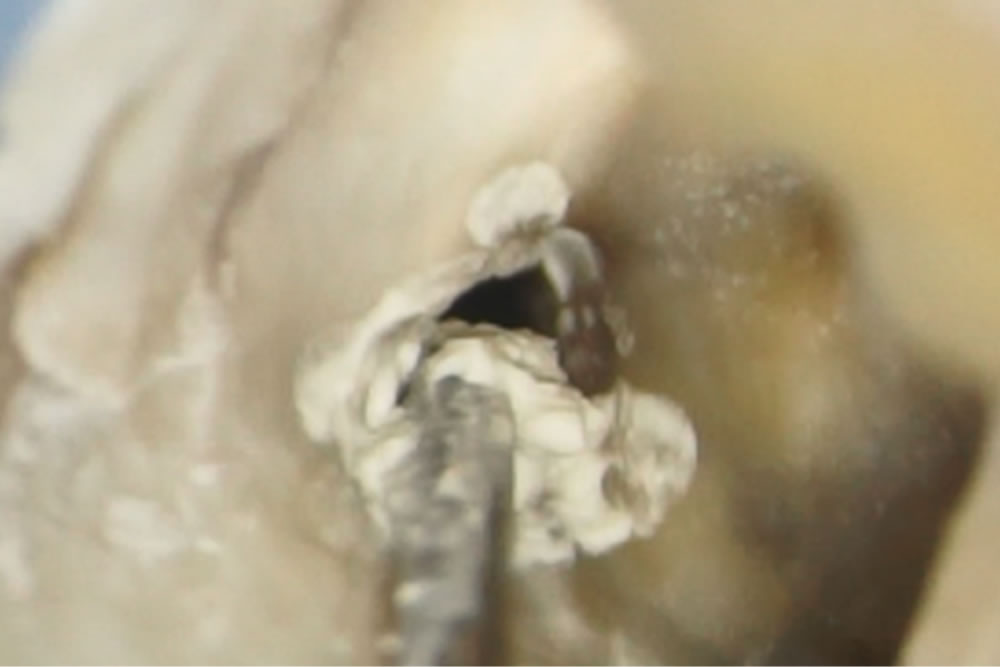

土台の形成

根の中に薬を詰めたら、歯の形を回復するためにまず土台となる部分を作ります。

レジンという歯の治療に用いるプラスチックの材料を、当該歯に流し込み特殊な光を当てて固めます。(マイクロスコープの強力なライトでも固まってしまうので遮光のため、視界が黄色くなっています。)

歯の表面をよく乾燥させ、接着のために歯の表面を薬品で処理します。ここでも呼気や唾液による接着不良を防止するため、ラバーダム防湿(ゴム製のシートで歯を口腔内から隔離)をしています。